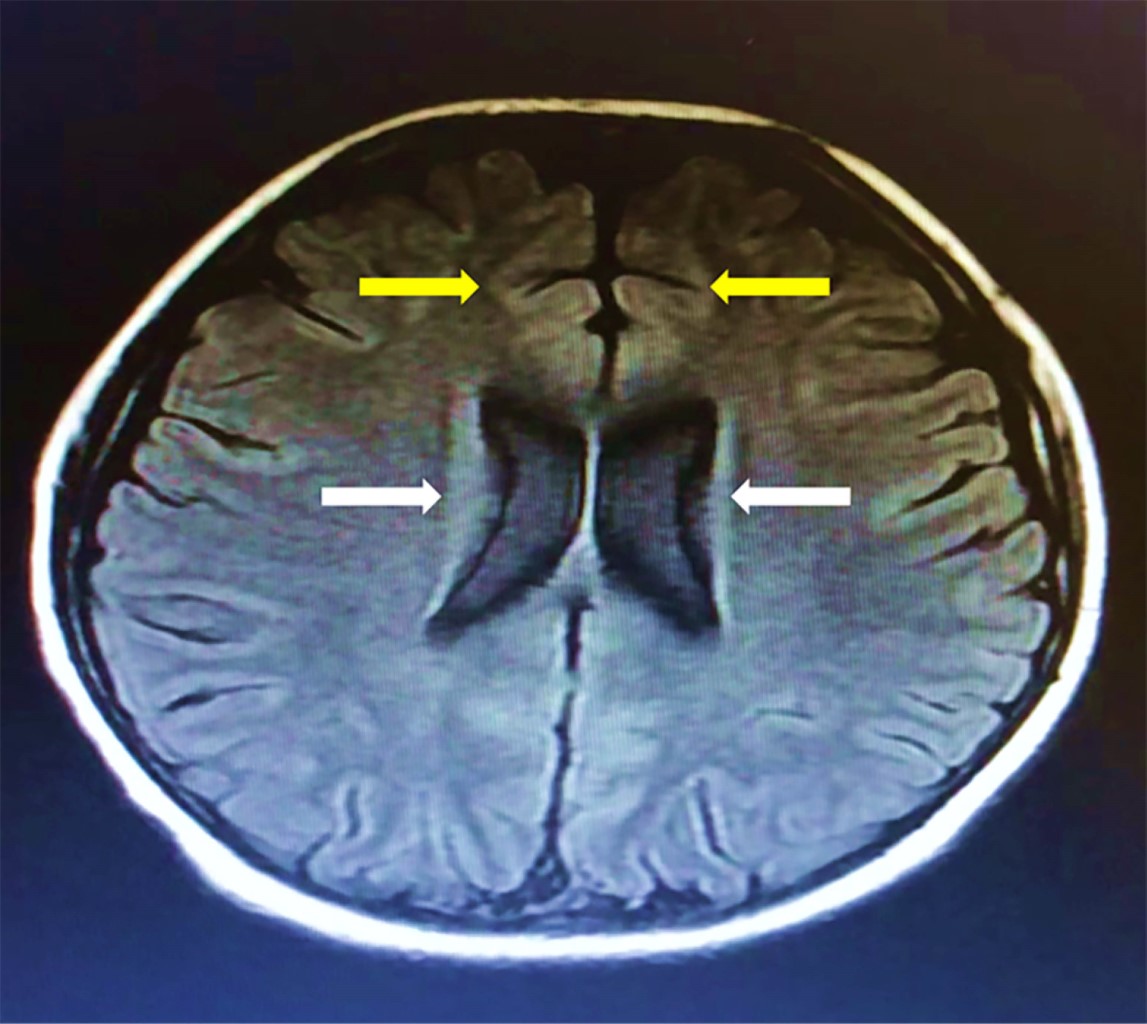

La biometría hemática con leucocitos de 18.75 × 1010/L, con neutrófilos de 82%. Los reactantes de fase aguda sin alteraciones. En el LCR se evidenció pleocitosis y positividad de anticuerpos inmunoglobulina G (IgG) para citomegalovirus y rubéola. Los hemocultivos periféricos y el cultivo de LCR sin crecimiento. Las imágenes de tomografía computarizada de cráneo (TAC) no mostró alteraciones. La resonancia magnética (RM) T2-FLAIR evidenció hiperintensidad en zonas paraventricular y en la corteza frontal (Figura 1).

Por otro lado, de acuerdo con Zhao y colegas, un resultado anormal en la RM podría asociarse a un peor pronóstico.1,4 En 50% de los casos se pueden encontrar hiperintensidad en la corteza frontal y en lóbulo temporal medial, además de la corteza cerebelosa, médula espinal y bulbo raquídeo.4,22,23